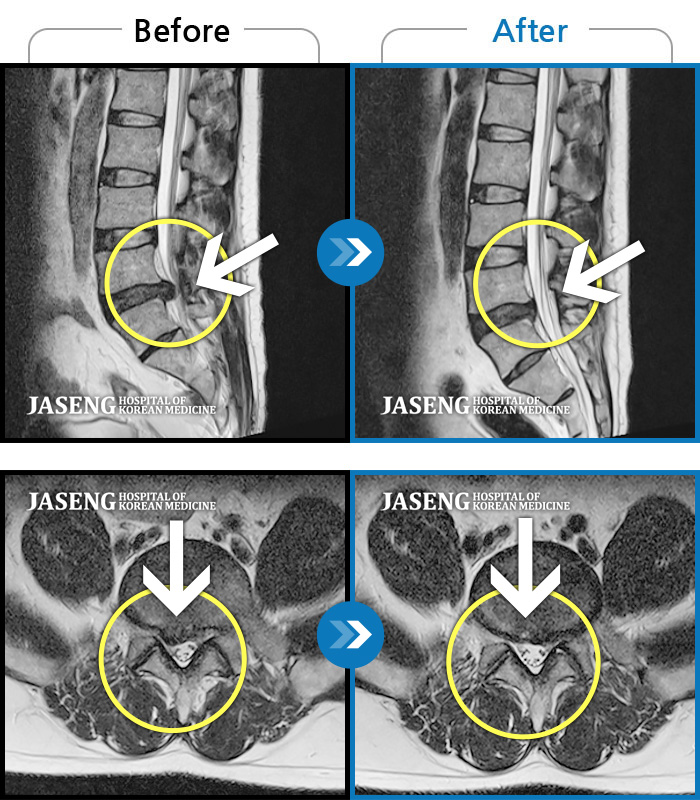

MRI 치료사례

종아리 통증